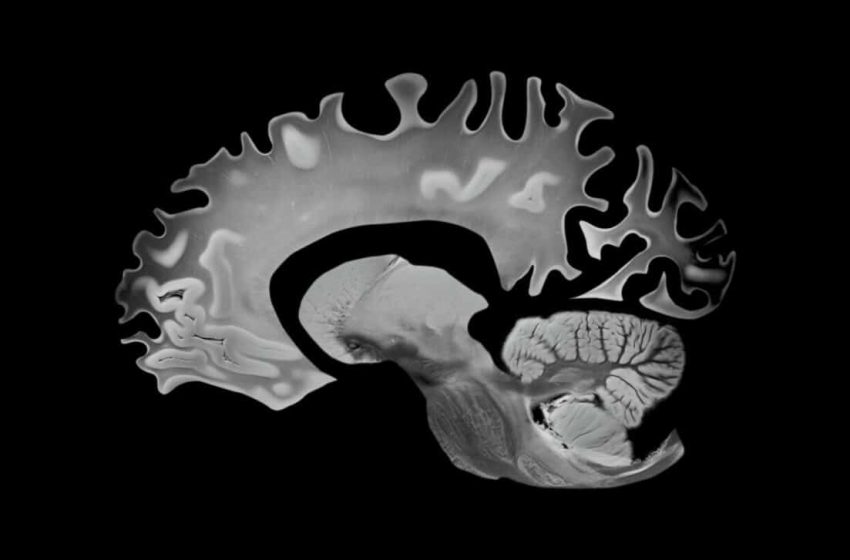

Why Gray Matter, and What’s Eating It

To understand why these findings matter, it helps to understand what’s at stake biologically. Gray matter, rich in neuronal cell bodies, dendrites and synapses, plays a key role in memory, learning and decision-making. Ventricular expansion, by contrast, reflects brain atrophy, tissue loss accompanied by the enlargement of cerebrospinal fluid-filled spaces.

In other words, both markers tracked in this study are well-established signals that the brain is shrinking in ways that eventually translate into cognitive decline.